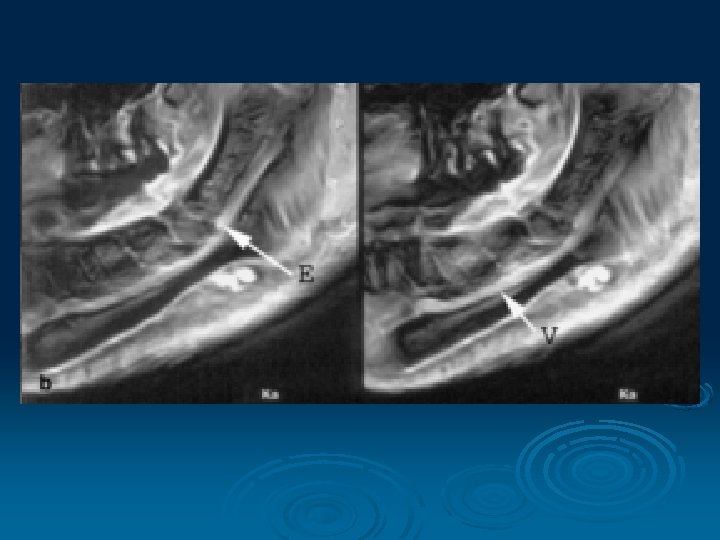

Magnetic Resonance Imaging § MRI allows visualization of soft tissue (muscles, fat, and internal organs) without the use of x-rays § Using two natural, safe forces, magnetic fields and radio waves § Can look “through” hard bones to examine soft tissue